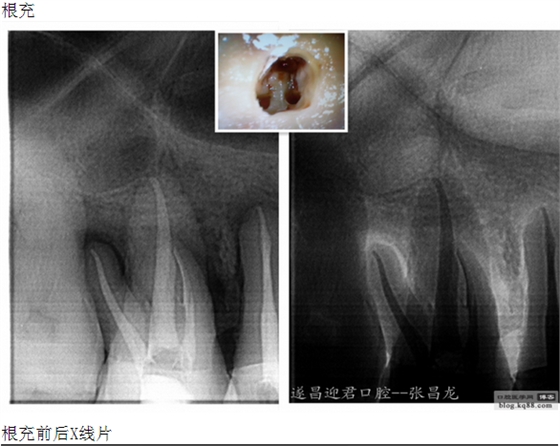

下面是我最近的一個(gè)患者,患者14,15,16均因楔狀缺損導(dǎo)致牙髓壞死,根管治療期間,16的近中頰根發(fā)生了斷針。

每個(gè)牙科醫(yī)生都不愿碰到器械分離,但常在河邊走,哪有不濕鞋的,我想大部分醫(yī)生根管治療中都發(fā)生過器械分離吧。在此就不在累贅那些造成根管器械分離的原因,醫(yī)生們也都知道那些。遇到器械分離莫慌,我們還是有挽救的余地。由于醫(yī)生的技術(shù)原因,設(shè)備原因,不是每個(gè)斷針都能取出來的。與對(duì)一部分?jǐn)噌樜覀兛梢試L試建立旁路通道,斷針與根管壁之間的間隙慢慢通入到工作長度,然后常規(guī)根管治療。

根管斷針牙科醫(yī)生永遠(yuǎn)的痛。小心操作,遠(yuǎn)離斷針。